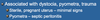

Uterine Rupture caused by Pyometra can lead to _____

Septic Peritonitis